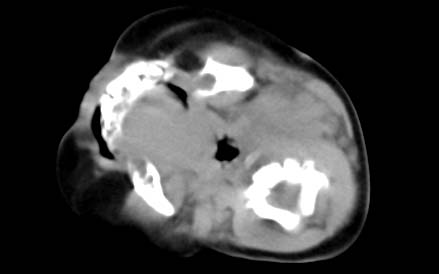

男,26天,发现左侧颈部包块5天,质较硬,患儿不哭不吵,无明显发热,头向右侧歪斜,其父母诉患儿出生时正常,昨天查血象wbc19.4×10的9次方/l,b超考虑来源于甲状腺的恶性肿瘤,我科认为肿块内有低密度区,而且病程发展较快,血象高,考虑炎性病变可能大。患儿年龄太小没做增强。请大家提出高见。

男,26天,发现左侧颈部包块5天,质较硬,患儿不哭不吵,无明显发热,头向右侧歪斜,其父母诉患儿出生时正常,昨天查血象wbc19.4×10的9次方/l,b超考虑来源于甲状腺的恶性肿瘤,我科认为肿块内有低密度区,而且病程发展较快,应该首先排除血肿,其次考虑感染

随访结果:炎症(患儿经过一星期抗炎治疗后颈部包块明显缩小,现已经正常)。